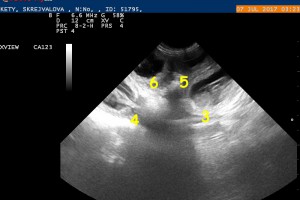

25.6. Březost potvrzena

Miminka jsou ještě velmi maličká, ale už teď víme, že jsou v Ketynčině bříšku nejméně 3 kousci, počítám, že spíš podstatně víc. Zatím jsou vidět jen plodové váčky velké celé 4 mm, počítat budeme až za týden